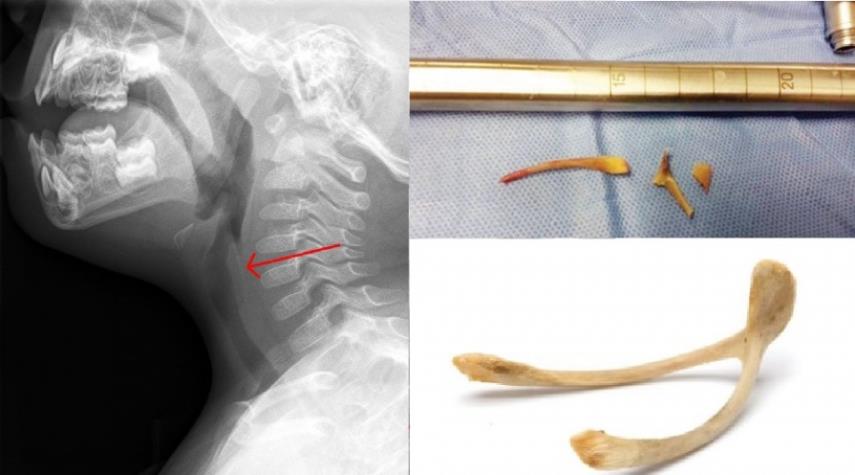

14 عاما سعال متواصل قبل اكتشاف ’السبب الصادم’ !

منوعات_الكوثر: عانت فتاة صينية على مدار 14 عاما من السعال المستمر وضيق التنفس، ولم تعرف السبب وراء هذه المشكلة الصحية على الرغم من زيارتها أكثر من طبيب، كلهم فشلوا في التشخيص، إلا واحد.

الجمعة 24 إبريل 2020 - 16:10 بتوقيت مكة